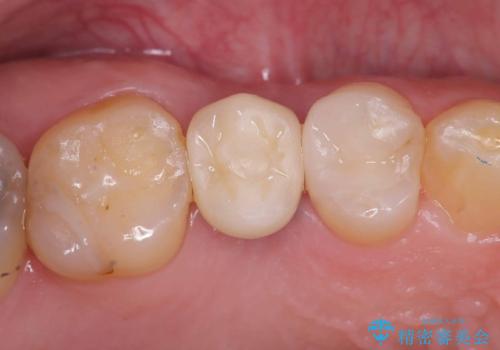

セラッミクインレー|オールセラミッククラウン|銀歯による二次カリエス|ラバーダムシート使用

銀歯の下の虫歯|オールセラミッククラウン|歯を長持ちさせるための治療|歯の神経を守る